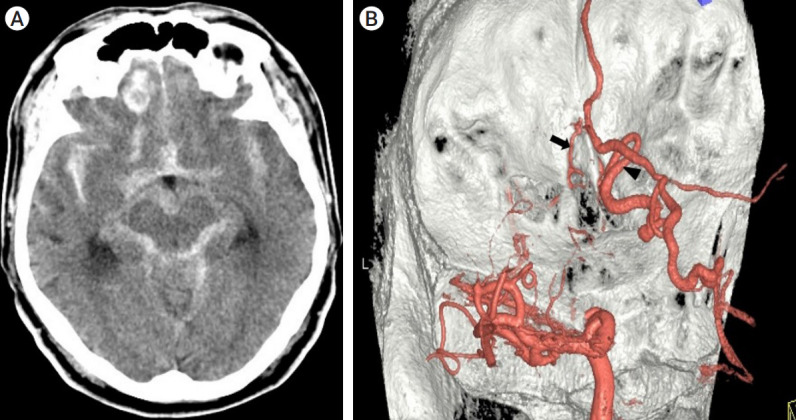

Objective: This study aims to investigate the efficacy of microsurgery with intraoperative indocyanine green (ICG) angiography as a treatment approach for ethmoidal dural arteriovenous fistula (DAVF).

Methods: Between January 2010 and July 2021, our institution encountered a total of eight cases of ethmoidal DAVF. In each of these cases, microsurgical treatment was undertaken utilizing a bilateral sub-frontal interhemispheric approach, with the aid of intraoperative ICG angiography.

Results: ICG angiography identified bilateral venous drainage with single dominance in four cases (50%) of ethmoidal DAVF, a finding that eluded detection during preoperative transfemoral cerebral angiography (TFCA). The application of microsurgical treatment, in conjunction with intraoperative ICG angiography, resulted in consistently positive clinical outcomes for all patients, as evaluated using the Glasgow Outcome Scale (GOS) at the 6-month postoperative follow-up assessment; six patients showed GOS score of 5, while the remaining two patients attained a GOS score of 4.

Conclusions: The use of intraoperative ICG angiography enabled accurate identification of both dominant and non-dominant venous drainage patterns, ensuring complete disconnection of the fistula and reducing the risk of recurrence.